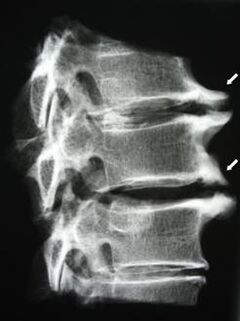

Алгачкы этаптарда мри колдонуу менен Остеофондроз аныкталды. Кийинчерээк патологияны рентгенографияны колдонуп диагнозу коюлушу мүмкүн. Моюнчанын омуртканын радиографтарында омурткалардын ортосундагы аралыкты азайып, бетине муундардагы патологиялык өзгөрүүлөрдүн жана остеофитоздун өзгөрүшү байкалууда.